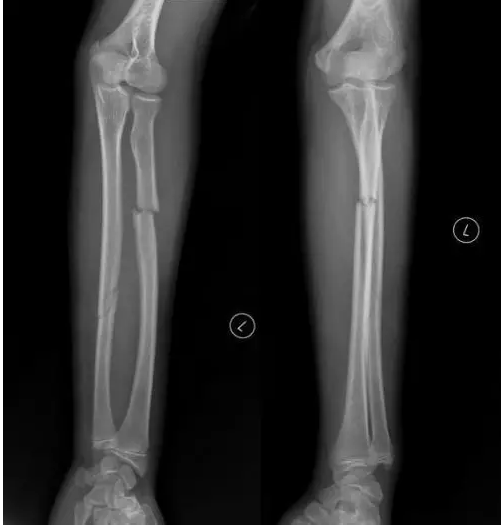

10、题干:男,56岁。左小腿外伤20分钟。结合X线片,此诊断为

A、左股骨骨折

B、左胫、腓骨双骨折

C、左腓骨骨折

D、左胫骨骨折

E、左尺、桡骨双骨折

答案:B

解析:该患者左小腿外伤,由图片可见胫腓骨透亮的骨折线,可判断该患者为胫、腓骨双骨折。(B对)